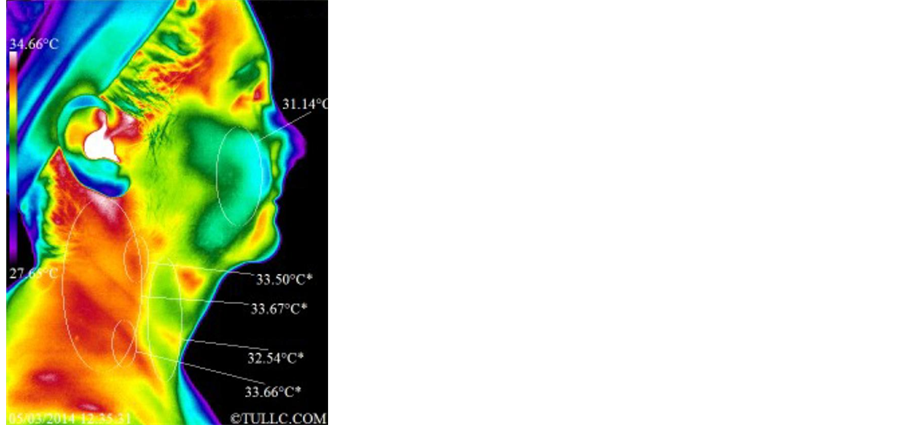

Subject C’s facial thermal images were analyzed using a span of 7.01˚C and positioning between 27.65˚C and 34.66˚C. Figure 10 shows that the temperature of her face decreased significantly (32.28˚C - 31.51˚C = 0.77˚C). The temperature of the supraclavicular regions did not change significantly and there is no significant change in

Before After

Figure 10. Subject C facial thermal images before and after one hour of grounding.

the asymmetry. Statistical details of the image markers are presented in Table 1. Figure 11 top images show Subject C’s right lateral side of the face and the images below show her facial left lateral side before and after the grounding session. The span and positioning is the same as in Figure 10. The right lateral side of the face (particularly the cheek) and the anterior neck cooled off while the posterior lateral aspects of her neck became warmer. On the left lateral side, we see a similar pattern i.e. the anterior neck cooled off while the posterior lateral aspects of the neck and the supraclavicular region warmed up. Statistical details are presented in Table 2. Figure 12 shows full anterior views of Subject C’s torso before and after the grounding session. The span and positioning for these images is between 27.77˚C and 34.78˚C. The regions marked with the letter “P” on the left thermal image are regions of pain as pointed out by the subject. The temperature of the torso in general decreased while the temperature of the region around the umbilicus increased but not significantly except for the region immediately above the umbilicus (32.12˚C - 30.87˚C = 1.25˚C). Statistical details are presented in Table 4.

3) Subject C―Female, Caucasian, 55, with history of uterine fibroids and lower pelvic pain

Subject C has a history of 2 fibroid in the uterus with intermittent lower pelvic pain ranging from 2 - 4, also right lower pelvic region. Figure 10 shows significant drop in temperatures over the following regions: forehead/eyes/orbit/surrounding nasal and oral regions. This is indicative of decongestion of the lymphatic/venous system of the head/neck with reduction in histamine type thermal markers surrounding the eyes and mouth. There is a significant reduction in periodontal inflammatory thermal markers that include the submandibular lymphatic system. The forehead heat pattern appears related to occiput/atlas entrapment of the suboccipital nerve/ vertebral artery resulting in dural influences affecting the 5th cranial nerve, thus causing frontalis/temporalis hypercontraction. In Figure 11, Subject C’s temporalis and temporal mandibular joint had improvement in myofascial activity and reduction in joint compromising effects on both laterals. Yet, increased posterior neck temperatures appear as if this subject was influenced by the elevation of the pillow and headrest of the reclining chair. Significant drops in temperature over salivary gland sites, while the external jugular vein and the scalene region demonstrated consistent temperatures on the pre-post study. The images of the full anterior views of the torso shown in Figure 12 presented a drop in temperatures over the acromioclavicular joints, around the clavicles, much of the spotted breast fibrocystic activity, significant drop in lymphatic/venous congestion heat pattern surrounding both nipple and areola, specially on the right side, and temperature decreases in lymphatic/ venous congestion below the breast. However, the hiatal region over the stomach had only a small drop in temperature, while small intestine and lower pelvic thermal markers increased by more than 1˚C with changes in abdominal distension pattern. Abdomen changes in pattern, like those observed around the umbilicus for this subject, are indicative of treatment/intervention effects (grounding). Autonomic control, or the lack there of, tends to produce consistent markers and patterns in the same geographical regions. Significant increased in vascular fluidity /digestive fluids/cerebral spinal fluid with improved autonomic control is related to intestinal lining motility. Clinical observations over the years have shown repeatedly that these changes in pattern do not happen without an external intervention.